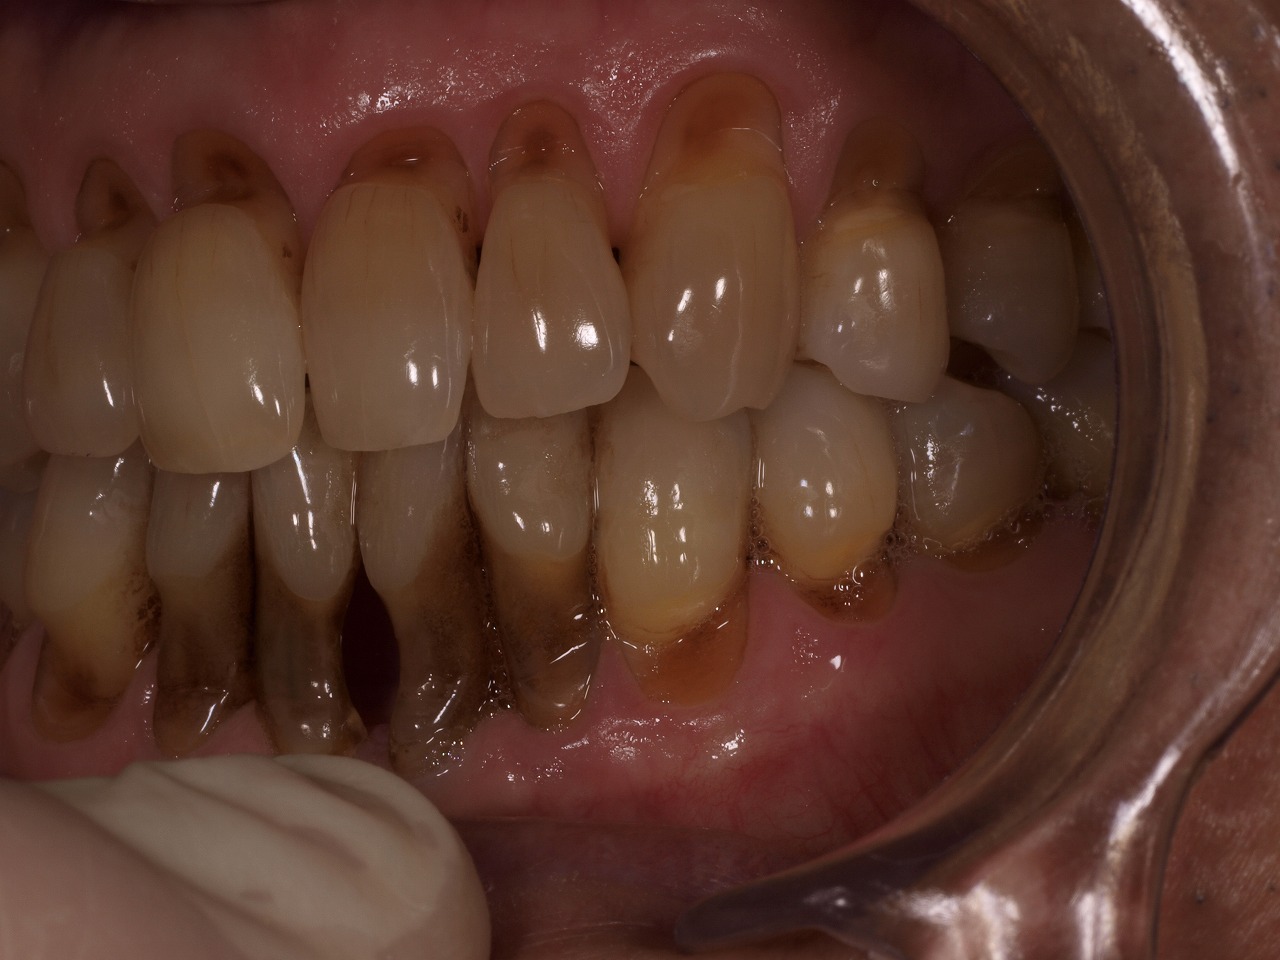

口腔内はこのような状態でくさび上欠損がひどく存在していました

右側面

左側面